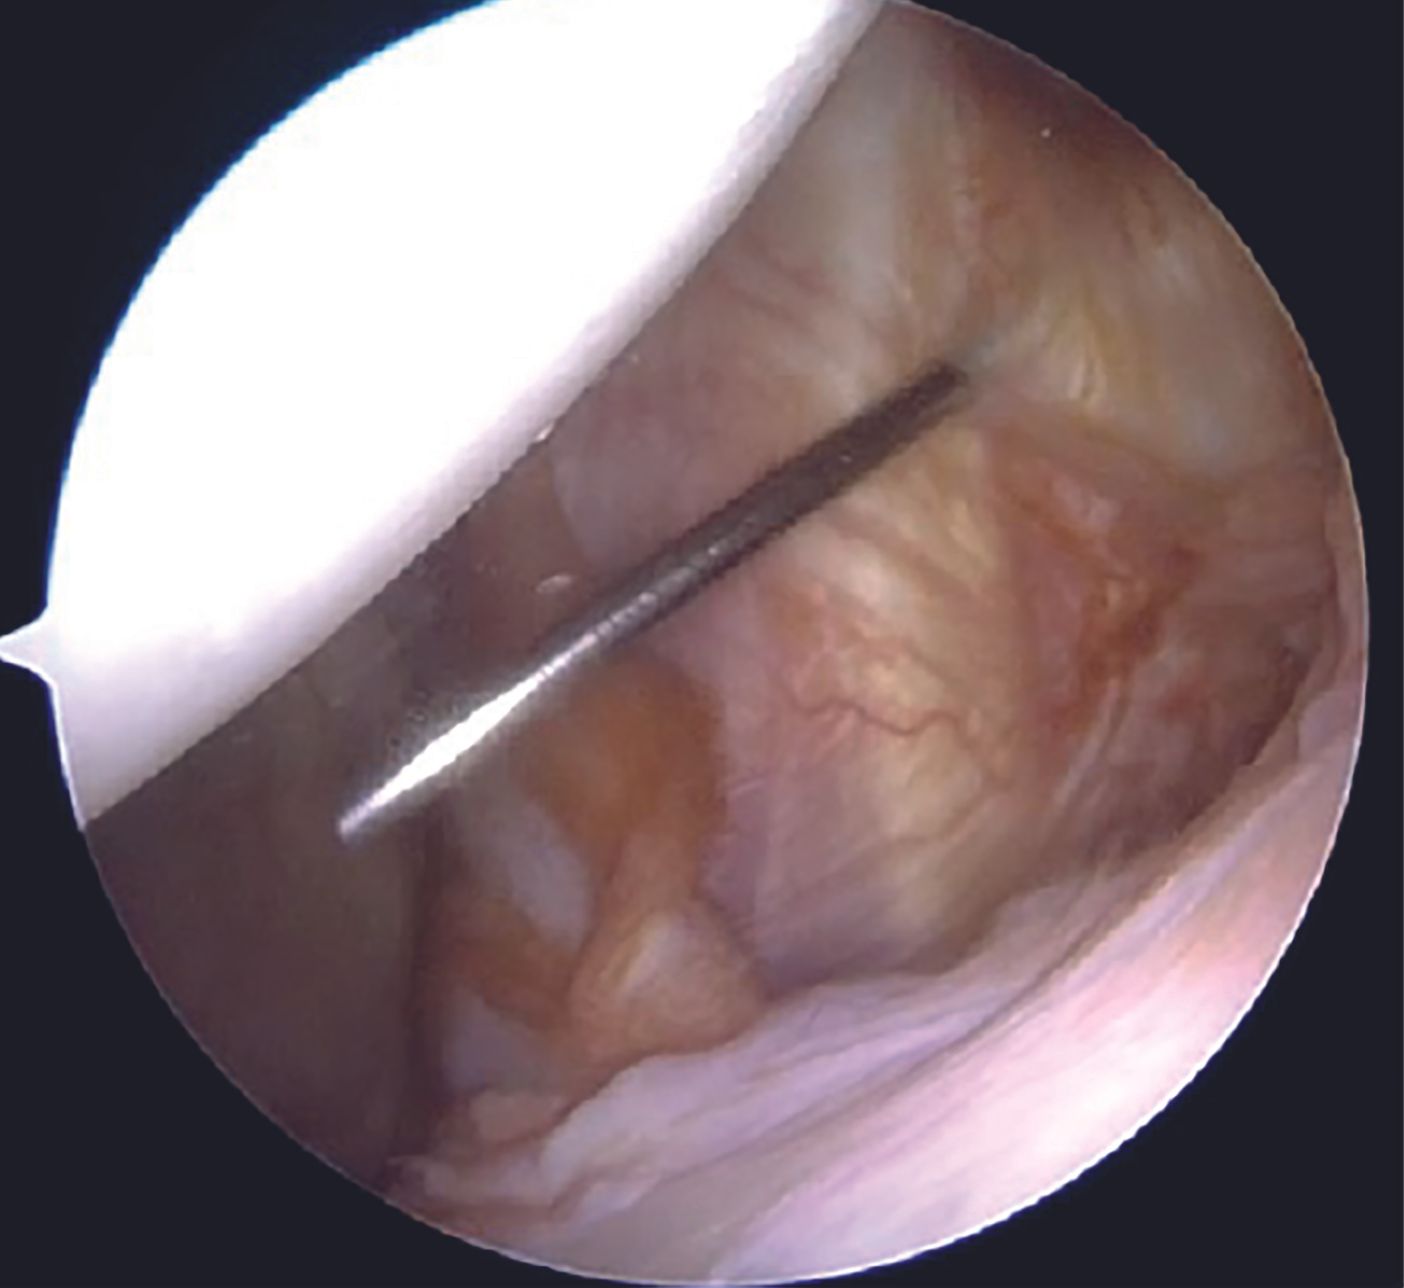

After the diagnostic arthroscopy, viewing portal is switched to the anterosuperior one, whereas the anteroinferior and the posterior portals act as the working portals with 7mm and 5mm cannulae, respectively. Labral tear extent is assessed with a probe (Figure 5).

Capsulolabral tissue is mobilized using 15 and 30 degree arthroscopic tissue elevators sequentially (Figure 6).